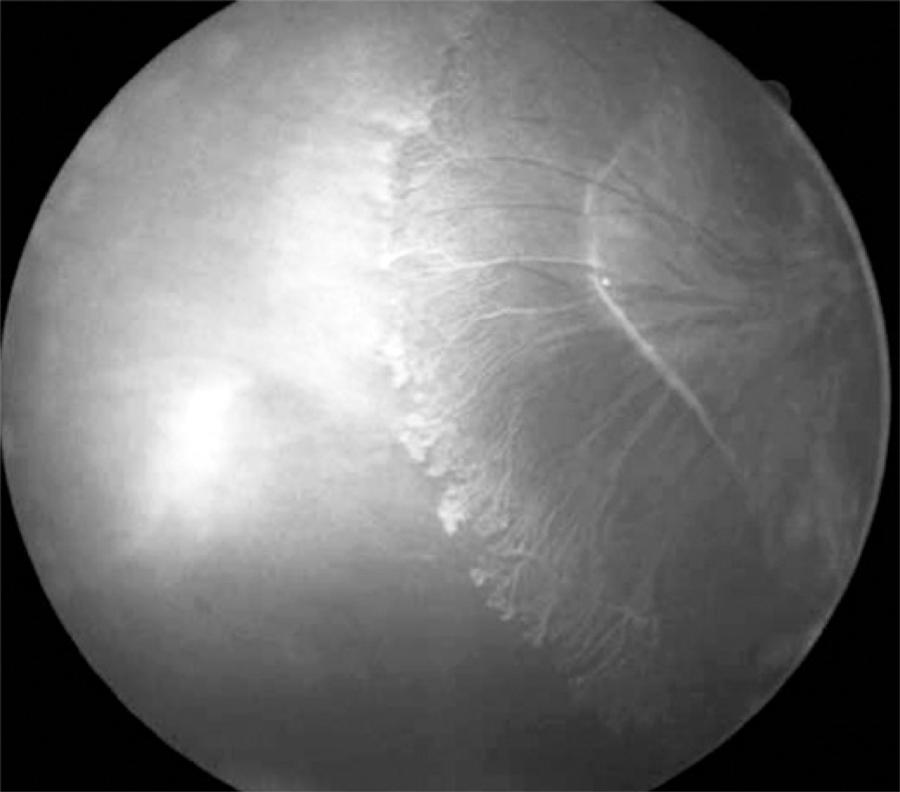

A 5-year-old girl presented with pain, hyperemia, and no light perception in the left eye in 2008. The intraocular pressure (IOP) in the affected eye was 47 mmHg. Ultrasound examination revealed fibrotic tissue extending from the posterior aspect of the lens to the optic nerve. The initial diagnosis was persistent hyperplastic primary vitreous (PHPV), although closed funnel retinal detachment could not be ruled out. The patient received medical treatment for the increased IOP and developed total hyphema 2 months later. The IOP decreased dramatically to 4 mmHg, and the condition of her left eye progressed to phthisis within a month. The best-corrected visual acuity in the fellow eye was 20/25. In 2010, her myopia increased to -4.00, and during retinal examination, an area of nonperfusion with new vessels was observed in the temporal peripheral retina (Figure 2). Her past medical history revealed a cutaneous rash during the neonatal period, which left pigmented lesions on the abdomen. Dental abnormalities were observed, including 12 missing teeth. Skin biopsy revealed an epidermis with hypopigmentation and a decreased melanocyte count, necrotic keratinocytes, and acanthosis. The dermis appeared thickened with a discrete inflammatory infiltrate and melanophages. Focal areas of degeneration of the basal lamina were present.

Figure 2 Case 2, right eye, pre-treatment. Fluorescein angiography showing an extensive area of nonperfused retina in the temporal periphery, along with fibrosis and new vessel formation.